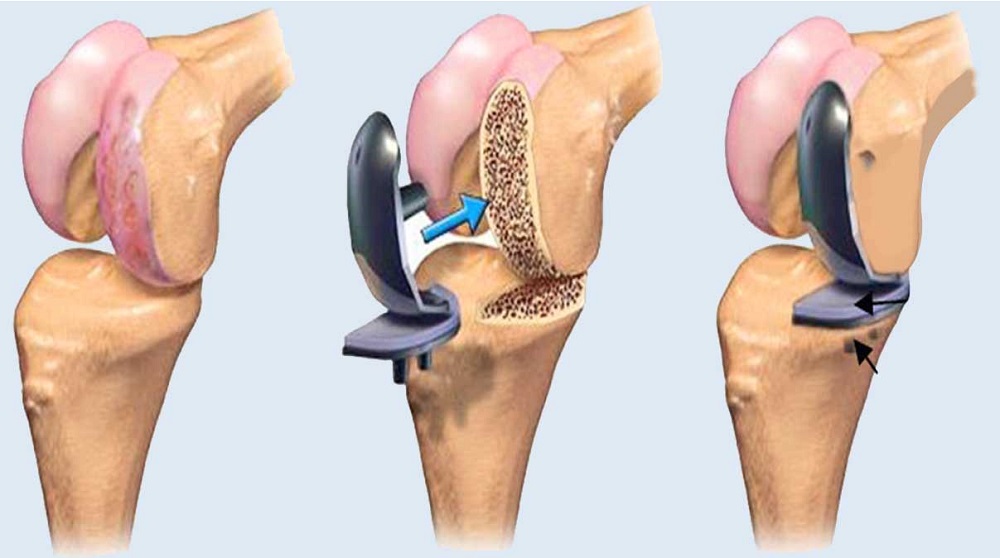

تمرینهاى روزها و هفتههاى اول بعد از تعویض مفصل زانو پایه و اساس بهبود کامل هستند. هدف این تمرینها کاهش ورم، جلوگیرى از خشکى مفصل، افزایش دامنه حرکت و فعالسازى عضلات اطراف زانو است. این تمرینها معمولا از روز اول یا دوم بعد از عمل و زیر نظر فیزیوتراپیست شروع مىشوند و بهتدریج پیشرفتهتر مىگردند.

انجام منظم تمرینها نهتنها درد را کمتر مىکند، بلکه سرعت بازگشت به راه رفتن طبیعى را افزایش مىدهد و از عوارضى مانند لخته شدن خون یا سفتى مفصل جلوگیرى مىکند. در کلینیک فیزیوتراپى خانه سلامت، این تمرینها براساس وضعیت هر بیمار شخصىسازى مىشود.

تمرینهاى روزهاى اول تا هفته دوم

در این مرحله تمرکز بر حرکت ملایم مفصل و فعالسازى عضلات است. تمرینها باید بدون درد شدید انجام شود و اگر درد زیاد شد، شدت را کاهش دهید.

تمرینهاى هفته دوم تا چهارم

در این مرحله دامنه خم شدن زانو و قدرت عضلات بیشتر مىشود.

تمرینهاى هفته چهارم تا هشتم

هدف در این مرحله تقویت بیشتر عضلات و بهبود تعادل است.